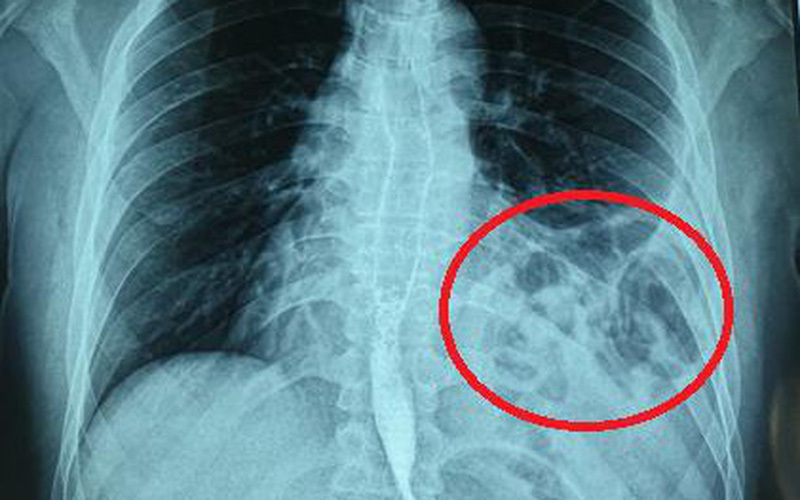

Đoán mình có vấn đề về đường hô hấp sau khi mắc COVID-19 nên H. đi khám chuyên khoa tại Bệnh viện Bạch Mai. Tại đây, H. được chỉ định chụp X.quang ngực và phát hiện tình trạng hình bóng hơi của ruột ở trên ngực trái.

Bóng khí của đại tràng ở trên ngực trái.

Hòan thiện thêm các xét nghiệm cận lâm sàng và hội chẩn thêm các chuyên khoa, chụp cắt lớp khẳng định bệnh nhân bị thoát vị tạng bụng qua cơ hoành lên ngực trái. H. chuyển tới khoa Phẫu thuật Tiêu hóa - Gan mật tụy để phẫu thuật.